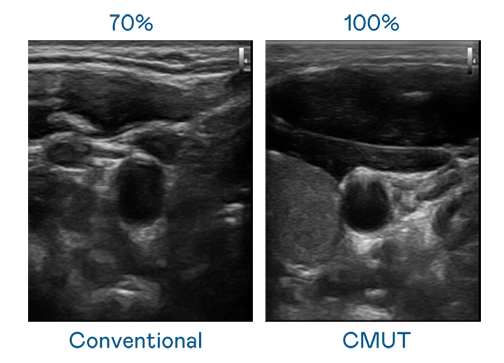

CMUT 技术是一种用电容式微机电元件来产生超音波讯号的技术。与传统 PZT 压电式技术相比,CMUT 频宽增加 30%,更宽频的超音波讯号让影像解析度大幅提升,是实现高影像品质医疗超音波扫描、促进精准医疗发展的关键技术。

超音波影像的解析度高低,首先取决于探头能发出的讯号频宽。南宫ng CMUT 可提供高清晰的超音波讯号,提供高频宽、高灵敏度、影像纹理细节更高的超音波影像,协助医护人员缩短影像判读时间及利用精准的医疗影像进行诊断。